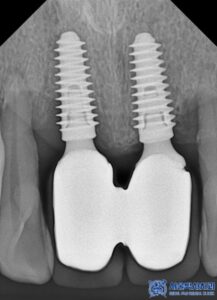

하지만 정밀 검진을 진행한 결과,

임플란트 고정체(뼈 속에 식립된 부분) 자체는

튼튼하게 자리 잡고 있었고,

문제는 그 위에 연결된 보철물과 지대주였습니다.

다만, 기존 보철물과 지대주는 교체가 필요하다고

판단하여 새로운 맞춤형 지대주와

보철물을 제작해드리기로 결정했습니다.